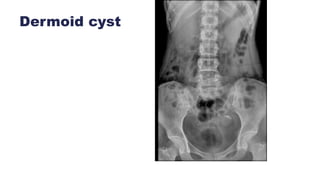

Dermoid cyst

• #26ย RADIOGRAPH KUB A faint radiopacity is seen overlying right renal shadow. Two arc like calcifications are seen in the pelvis on both sides. Sub-optimal bowel preparation . Pro-peritoneal fat lines are maintained. Visualized renal shadows is normal. Visualized psoas shadows are normal. Visualized bones and joints are normal. IMPRESSION:ย  ? Right renal / GB calculus Two tubo-ovarian stromal fibroid calcifications. Mature cystic teratomas are encapsulated tumours with mature tissue or organ components. They are composed of well-differentiated derivations from three germ cell layers (ectoderm, mesoderm, and endoderm). Ectoderm โ€“ hair, teeth, nails